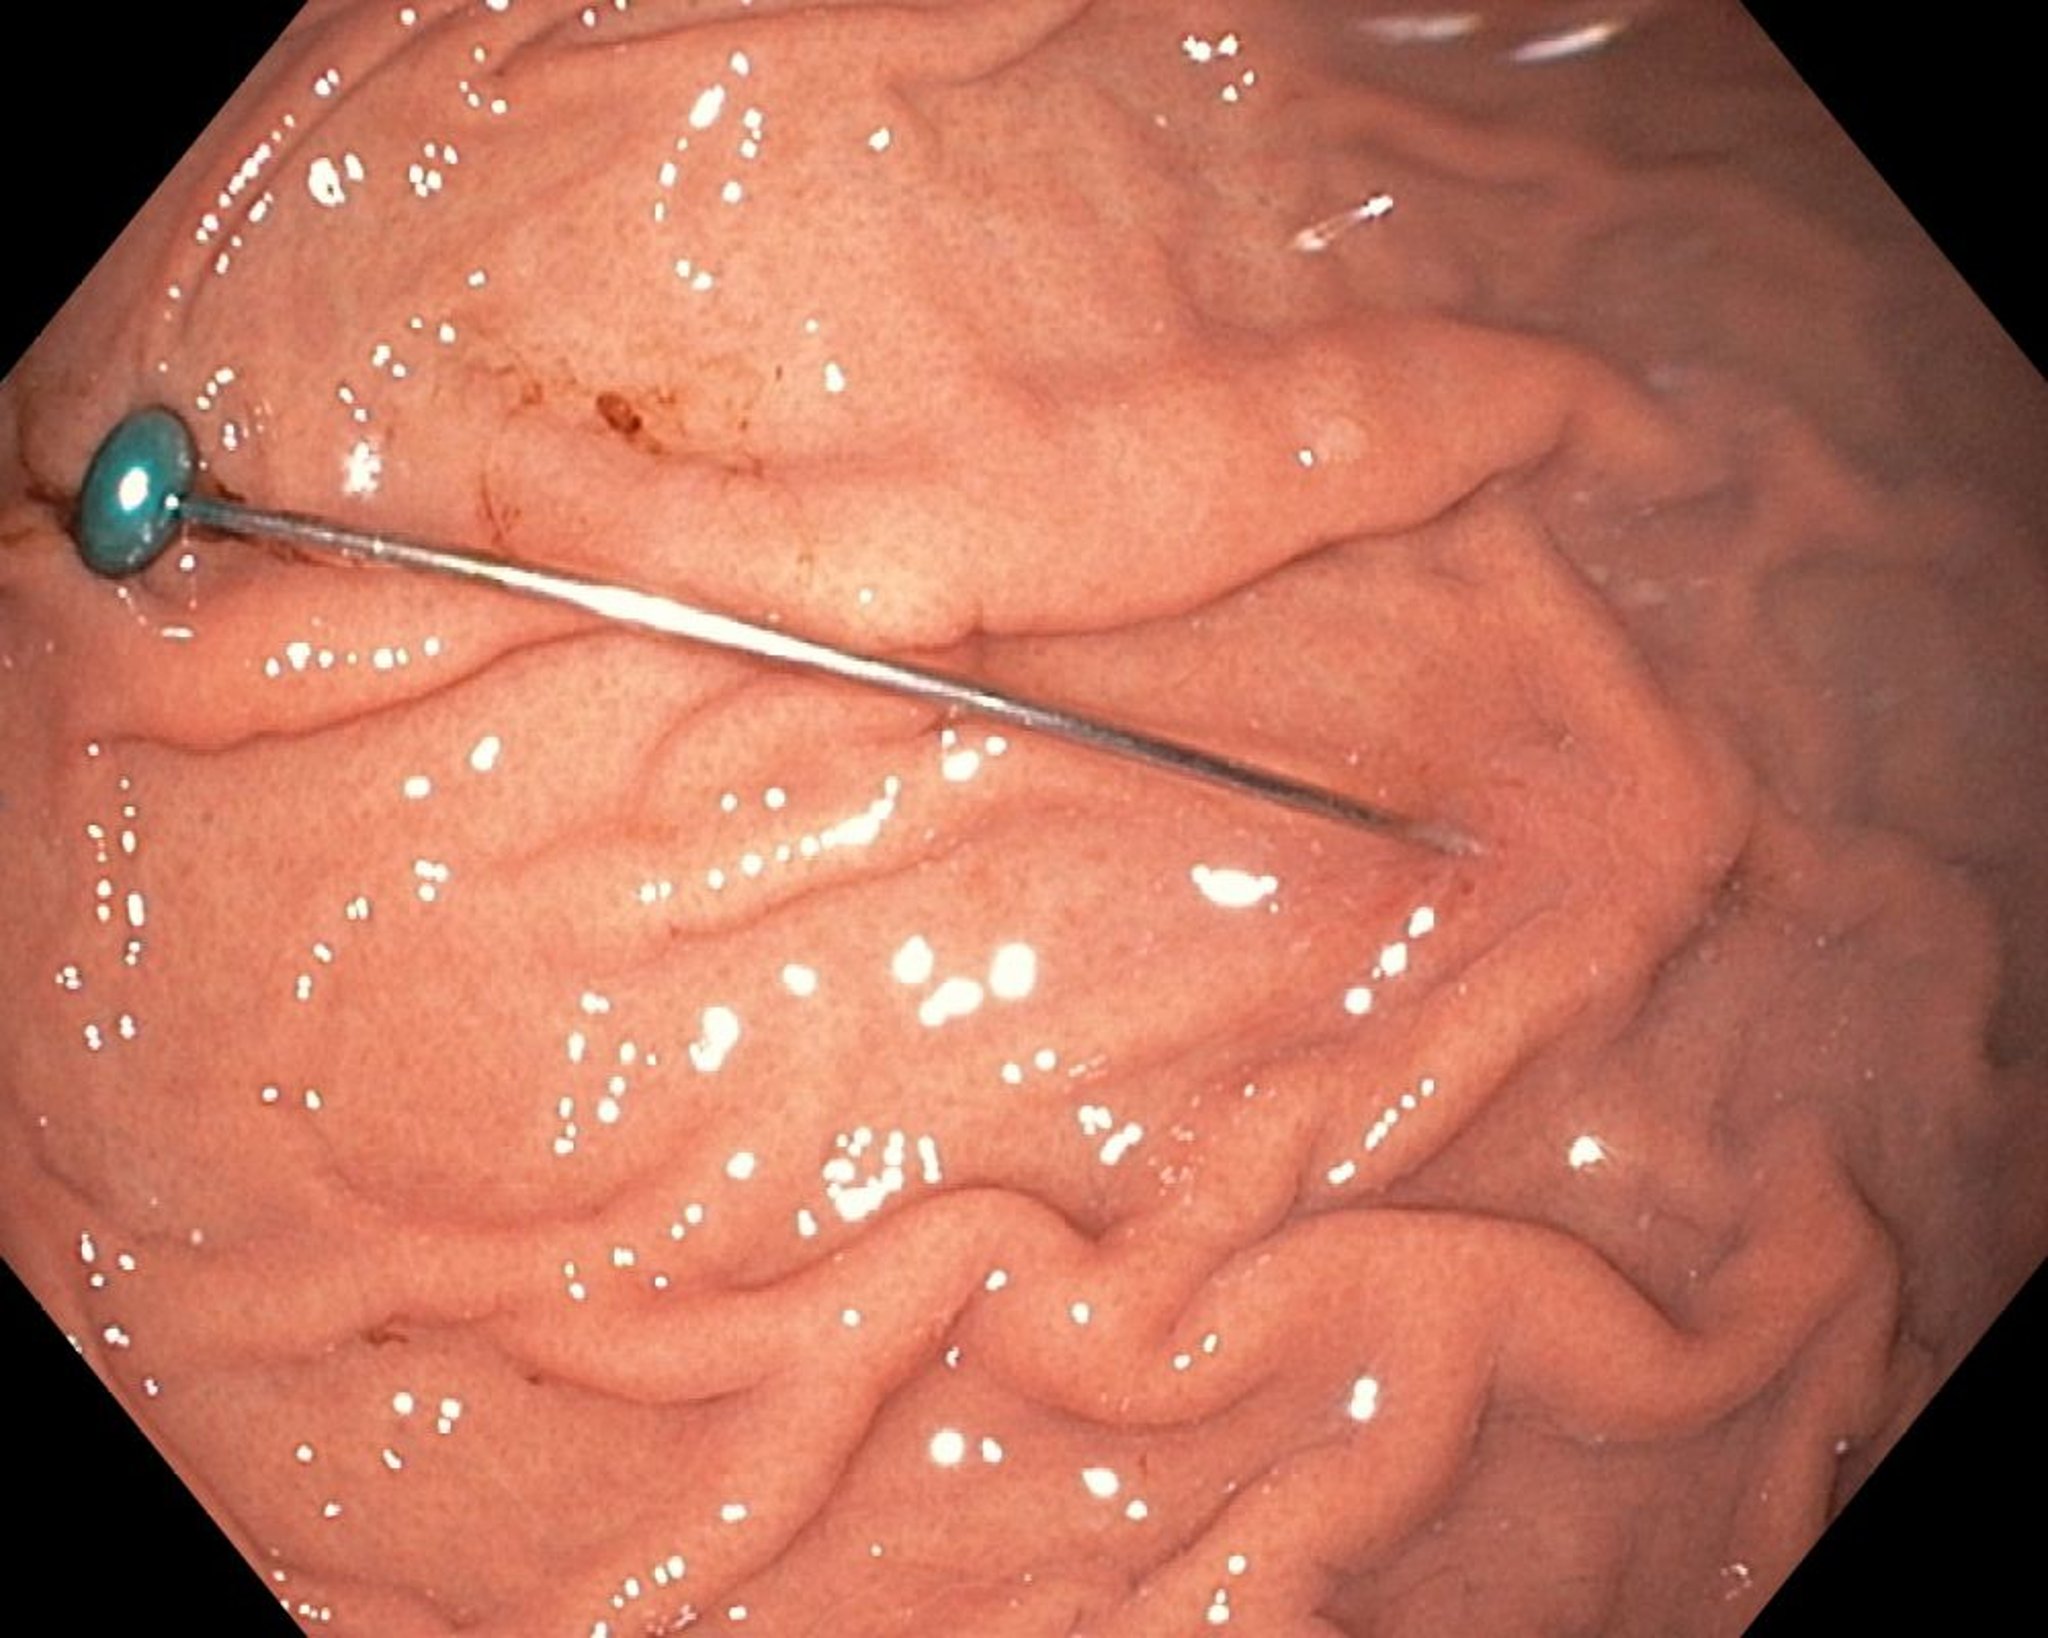

पेट में तीखी बाहरी चीज़ (एंडोस्कोपी)

यह छवि पेट में तीखी बाहरी चीज़ दिखाती है।

छवि उदय शंकर, MD द्वारा प्रदान की गई है।